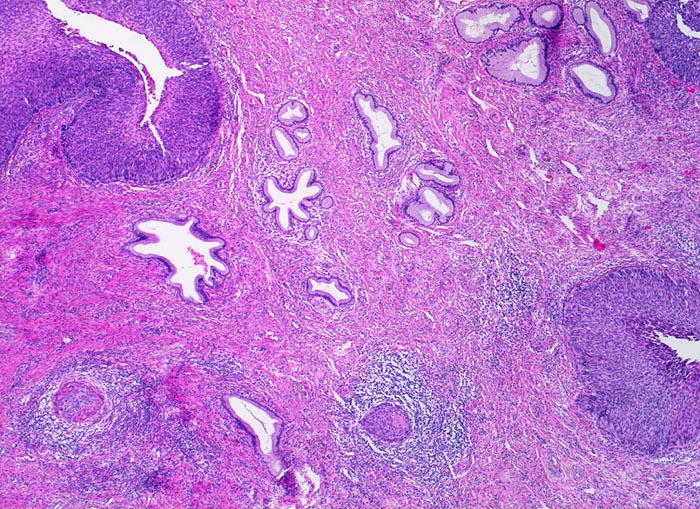

Das Carcinoma in situ wird in der Bethesda Klassifikation zusammen mit der mittelschweren und der schweren Dysplasie eingeteilt als high grade squamous intraepithelial lesion (HSIL). Im Vergleich zur schweren Dysplasie nehmen Grösse und Hyperchromasie der Kerne weiter zu. Die Zellgrösse entspricht dem Basalzelltyp. Das Chromatin ist grob verklumpt und unregelmässig verteilt. Der Kernhintergrund ist hell. Dadurch entsteht die an ein Leopardenfell erinnernde Kernstruktur. Grosse Nukleolen sind verdächtig auf eine bereits vorhandene Mikroinvasion (zweites Bildbeispiel). Zytologische und histologische Aufnahmen stammen von verschiedenen Patientinnen.